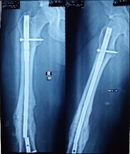

Case-I

19 years, male;

Broken ILIMN of femur (Ipsilateral fracture shaft of femur with tibia and fibula, H/O-poly-trauma) (Figure 1-4). Infection and non-union are the morbid complications of fracture management. Infections are more common in open fracture also caused by superficial surgical site infection. The incidence of infection in closed long bones fracture 1-2% and it is higher in open fracture, 5% Gustilo type-Ⅰ, 10% Gustilo type-Ⅱ and 15% Gustilo type-Ⅲ8 and surgical site infection (SSI) is 3.6 to 4.8%.9 The fracture complexity and soft tissue damage are the critical factors, influence the risk of infection.

Figure 1 X-ray broken IM nail after fall.

Figure 2&3 Post-operative x-ray after Ilizarov operation.

Figure 4 X-ray after union.